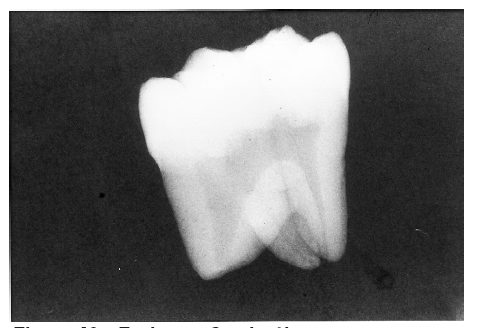

Figure 40 - Fusion or Gemination

Figure 40

Fusion is defined as the joining of two originally separate teeth through the dentin, or through the dentin and enamel. In contrast, gemination represents incomplete division of what should have been two separate teeth. Fusion may involve supernumerary teeth, and gemination may occur in quadrants also affected by partial anodontia; thus, counting the teeth in the affected area is of limited diagnostic value. Regardless of which process initiated the error, it is practically impossible to distinguish between fusion and germination, and in either case, the tooth will appear much like that in Figure 40

The distinction between fusion and germination is primarily of academic interest and thus, the etiology is of less clinical concern than is the presence of the condition and the potential ramifications involved.